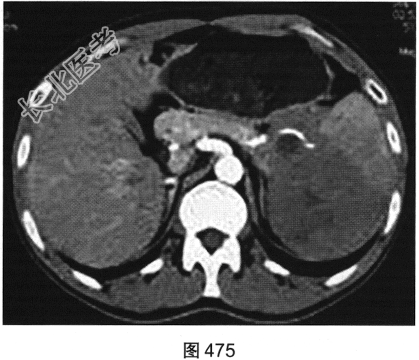

- 多项选择题3.[提示]患者行CT动态增强扫描,如图474~图476所示。对CT图像描述正确的是( )

A、脾血管被病灶侵犯

B、CT平扫呈不均匀低密度

C、胰腺被病灶侵犯

D、病灶门脉期轻度强化

E、病灶边界清晰,具有包膜

F、病灶动脉期无强化